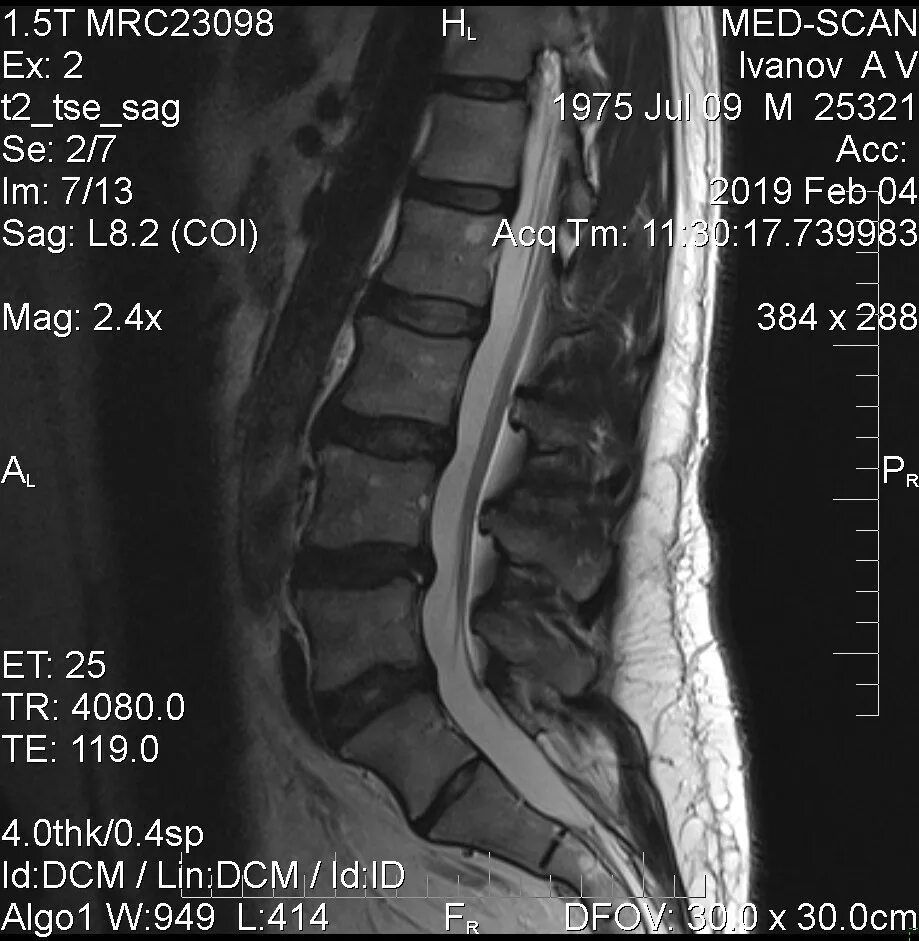

При каких размерах грыжи делают операцию